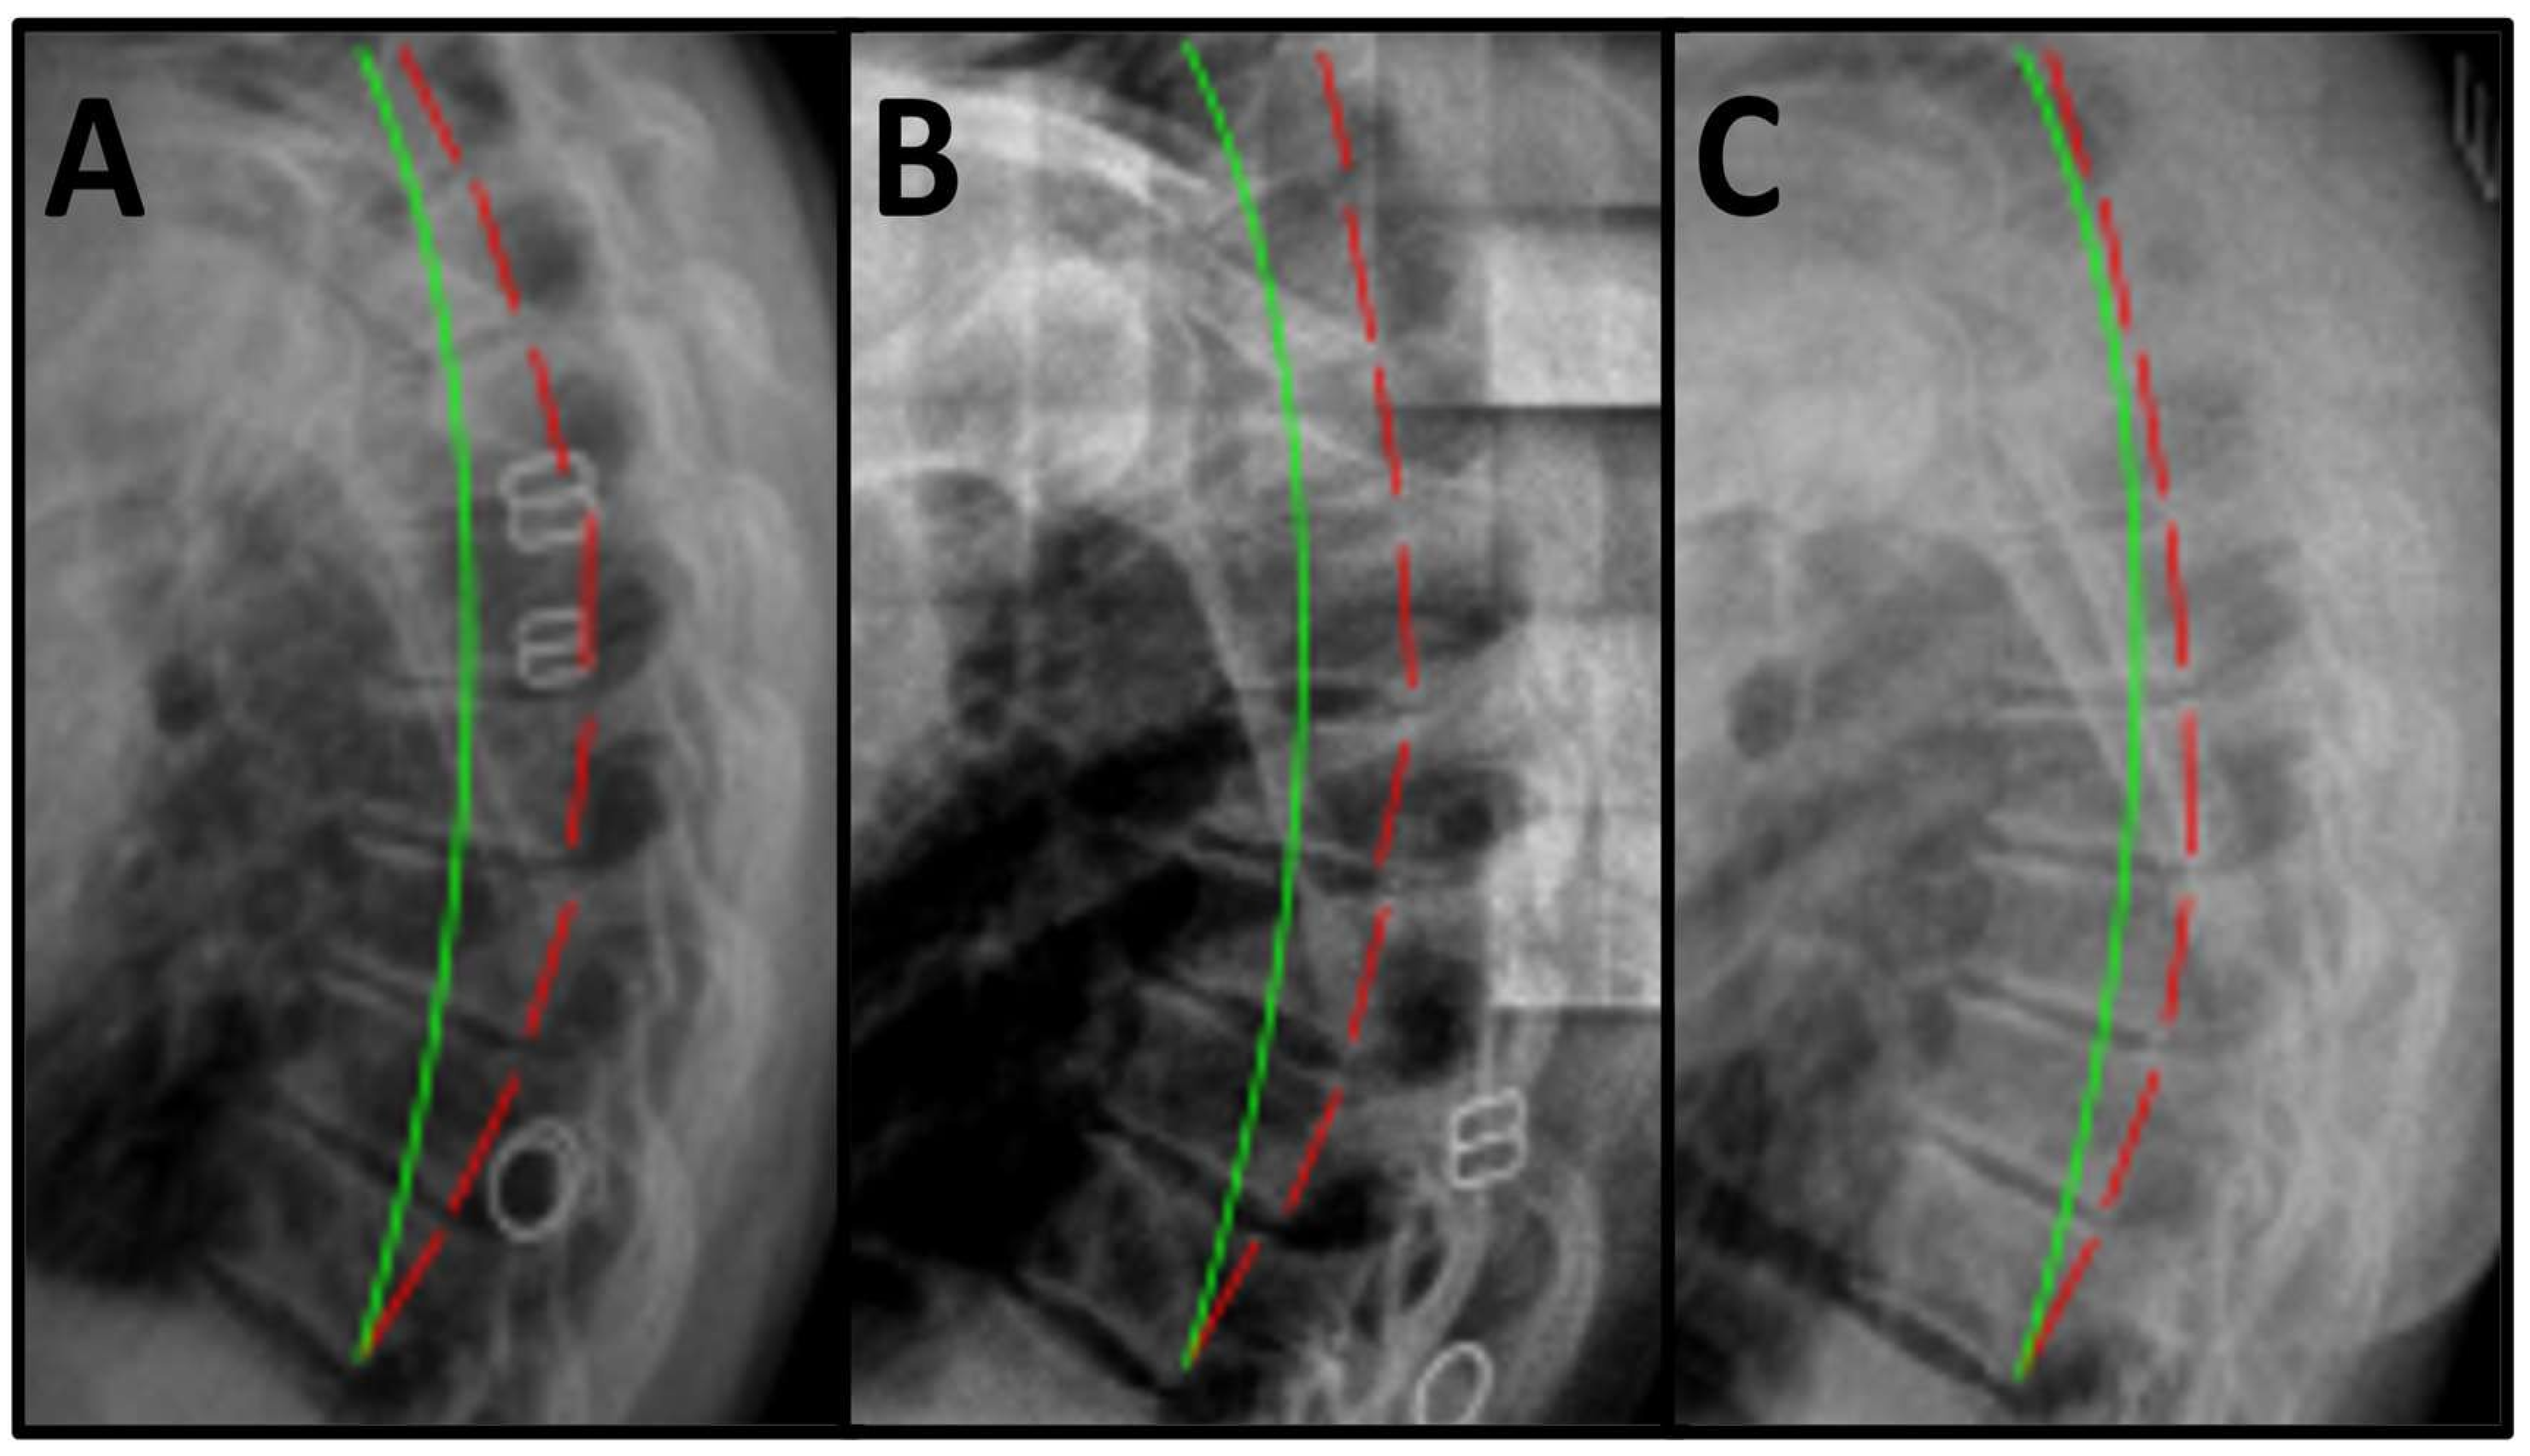

| Radiographic Findings | T1–T12 ARA (Ideal is 44°) |

|---|---|

| Pre-Treatment | 66.2° |

| Post-Treatment | 45.2° |

| Long-Term Follow-up | 47.7° |